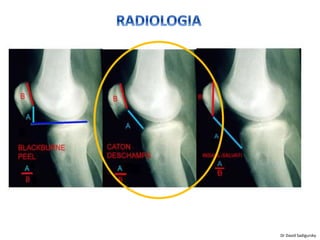

• Radiografia

– Pouco valor

– Alinhamento tíbio-

femoral

– Altura patelar

– Displasia Troclear

Axial da patela – 45°

Ângulo de congruência – 6° a +- 11°

Ângulo do Sulco 138°